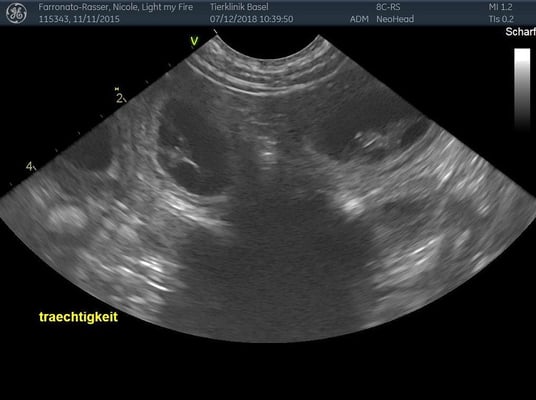

7. Dezember 2018. Der heutige Ultraschall am 24. Trächtigkeitstag hat gezeigt, dass Light trächtig ist! Wir freuen uns riesig auf Mitte Januar und hoffen auf eine Kiste gesunder kleiner Labradore!